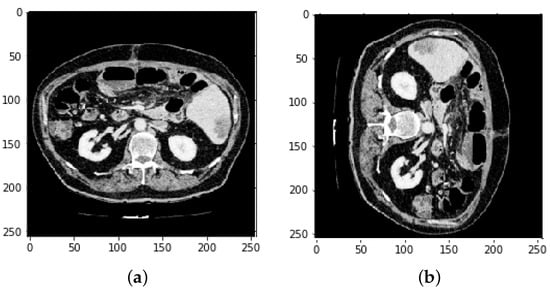

3.2. CT and MRI Images Preprocessing